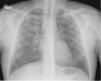

Descripción de los casosSe diagnosticaron 5 casos de TB-MDR cuyas características clínicas se describen en la tabla 4. Fue muy llamativo el retraso en la obtención del diagnóstico microbiológico entre el primer caso que se demoró 4 meses y el último que se obtuvo en 72 horas, relacionado con la disposición de la técnica de reacción en cadena de la polimerasa (PCR) en muestras respiratorias, en el hospital de referencia. El caso 1 o índice presentó una demora añadida en su diagnóstico al ser interpretado inicialmente como una neumonía comunitaria, en la figura 1 se muestra la radiografía de tórax.